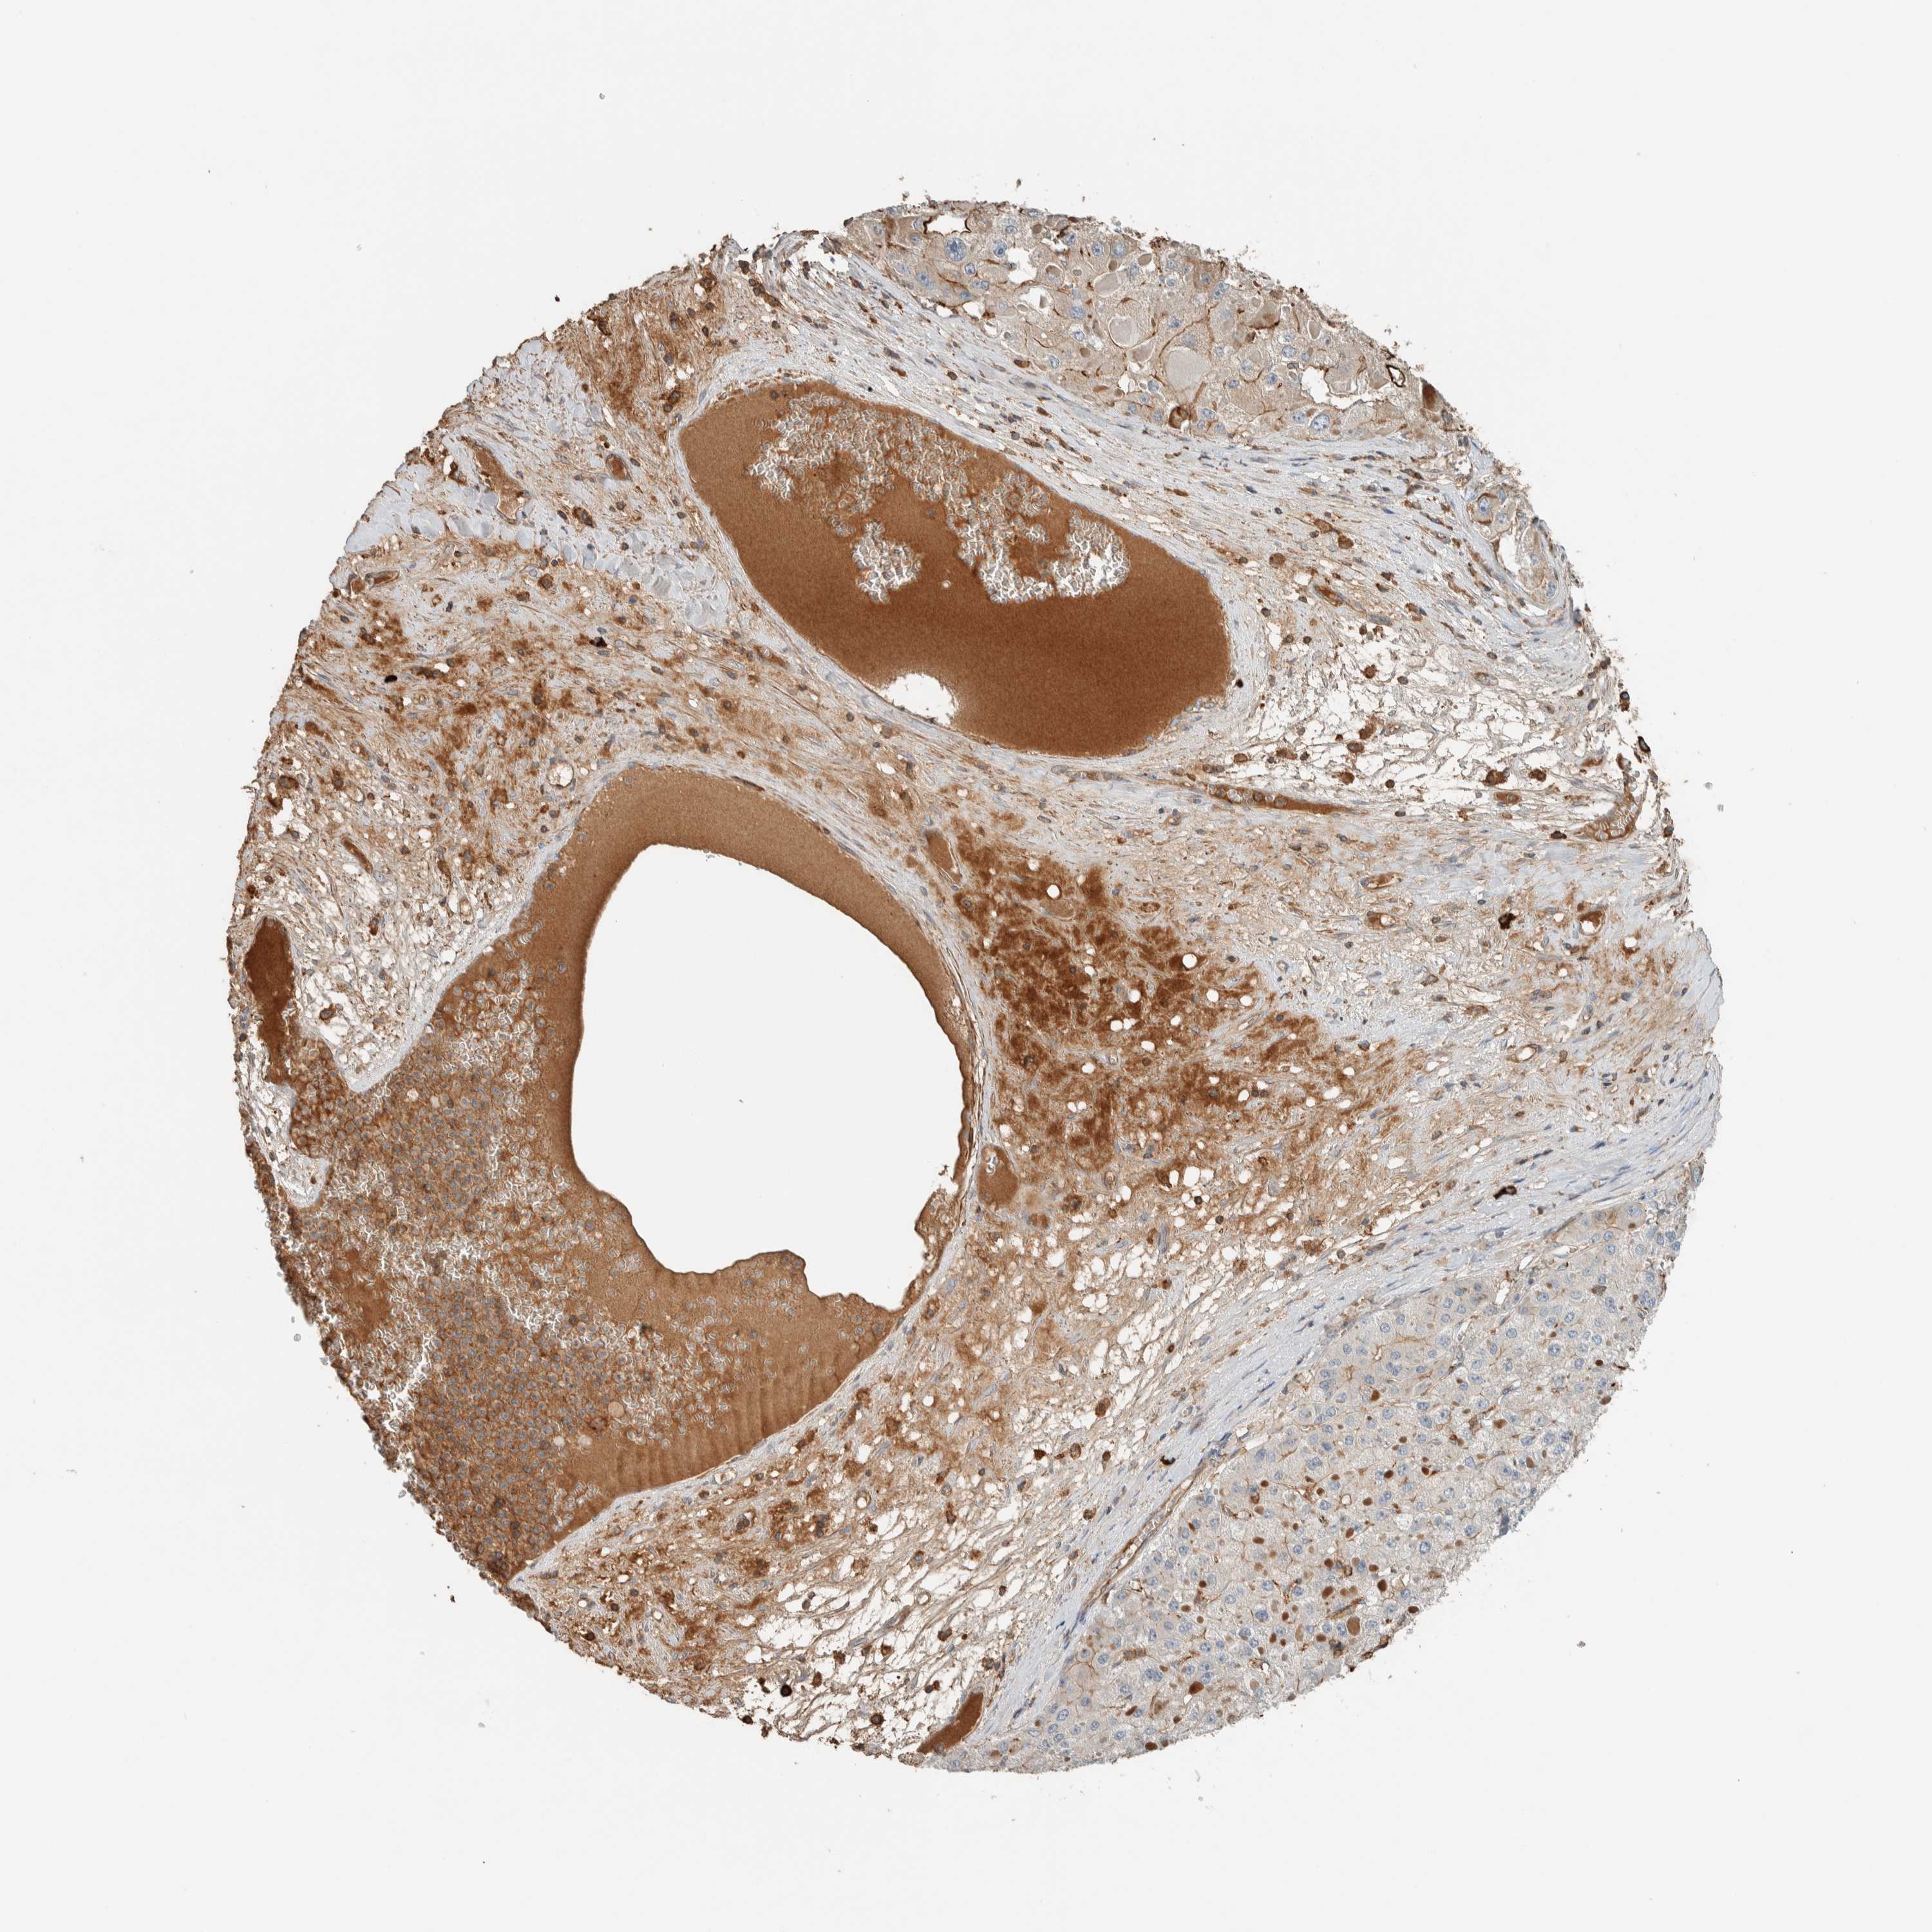

LIVER CANCER - Protein expressioni

A mouse-over function shows sample information and annotation data. Click on an image to view it in a full screen mode. Samples can be filtered based on level of antibody staining by selecting one or several of the following categories: high, medium, low and not detected. The assay and annotation is described here.

Note that samples used for immunohistochemistry by the Human Protein Atlas do not correspond to samples in the TCGA dataset.

Antibody stainingi

Antibody staining in the annotated cell types in the current human tissue is reported as not detected, low, medium, or high, based on conventional immunohistochemistry profiling in selected tissues. This score is based on the combination of the staining intensity and fraction of stained cells.

Each image is clickable and will lead to virtual microscopy that enables deeper exploration of all samples and also displays staining intensity scores, fraction scores and subcellular localization as well as patient and tissue information for each sample.

Antibody HPA023559

Antibody HPA023564

Antibody HPA044971

Antibody CAB031916

Staining

High

Medium

Low

Not detected

Intensity

Strong

Moderate

Weak

Negative

Quantity

>75%

75%-25%

<25%

None

Location

Nuclear

Cytoplasmic/membranous

Cytoplasmic/membranous,nuclear

Cholangiocarcinoma

Carcinoma, Hepatocellular, NOS